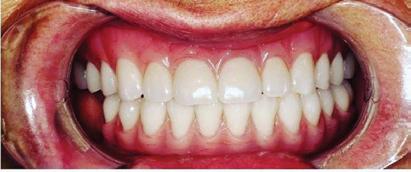

Can just four implants replace all of the teeth on the top or the bottom of your mouth? Thanks to advances in dental implant technology, that answer is a resounding yes.

Believe it or not, tooth loss is extremely common among adults, especially as we age. In fact, more than 35 million people in America are missing all of their upper and/or lower teeth. Rather than living with the discomfort and hassles of dentures, many people are opting for what is called “all-onfour” dental implant restoration.

All-On-Four: One Full Arch Of Teeth, Four Dental Implants

Here’s where it gets really interesting: You do not need a dental implant for each and every one of your missing teeth. All you need is four precisely placed implants on the top of your mouth, and four on the bottom, to restore your full smile. That’s the beauty of the all-on-four. And because the implant is made of titanium, it has the unique ability to fuse to living bone and function as part of it. So eventually, the dental implant becomes part of the jawbone and serves as a strong, long-lasting foundation for your new teeth.

this bone fusion has another important benefit: it prevents future bone loss in the jaw. This helps to maintain a more youthful facial structure – and better oral health. But perhaps the biggest surprise about the all-on-four is how quickly it can transform your life.

All-On-4 Dental Implants: A Reason To Smile Again

To fully understand this remarkable technique for replacing teeth, you should first understand what a dental implant is. An implant is a small titanium screw that fits inside your jawbone and replaces the root-part of a missing tooth. Minor surgery is required to insert the implants. Once the implant is in place, a crown is attached to give you a highly realistic-looking and functional prosthetic tooth.

Besides ensuring that your implants are permanently fixed in place, this bone fusion has another important benefit: it prevents future bone loss in the jaw. This helps to maintain a more youthful facial structure – and better oral health. But perhaps the biggest surprise about the all-on-four is how quickly it can transform your life.